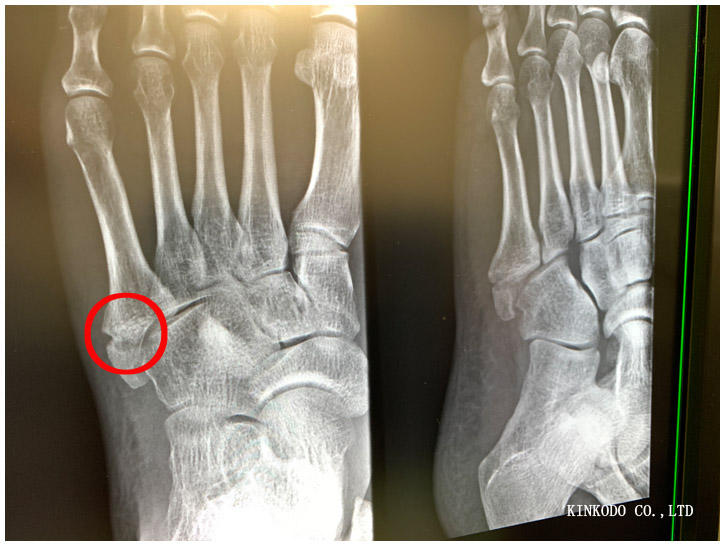

今日も骨折の受診。さてどうなっているか?

いい状態ですが、完全にくっついているわけではありません。気を付けて走るようにとのことで、大阪マラソン前にもう一度レントゲンを撮ることに。